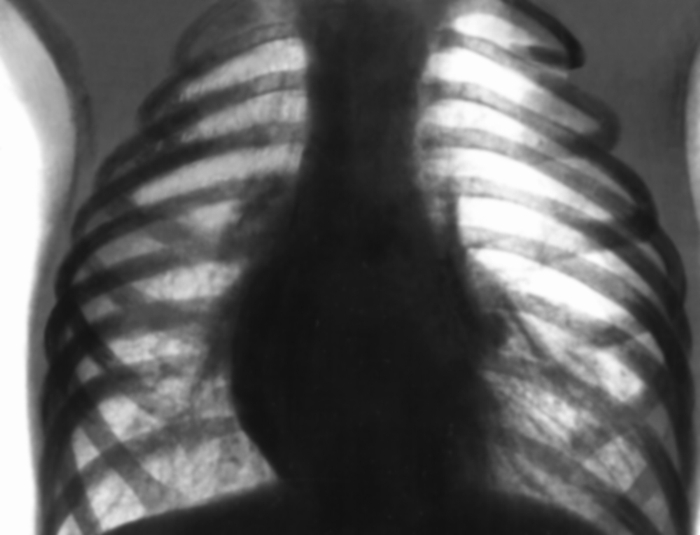

Диагностика эмфиземы легких основывается на осмотре больного, рентгенограмме органов грудной клетки, чтобы исключить другие возможные причины симптомов, КТ для оценки тяжести повреждения легких и их локализации, определение уровня кислорода в крови.